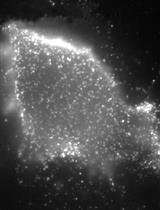

Cover of Cancer Cell, featuring study using the protocol.

Nov 2012